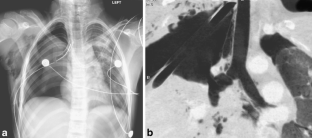

Fig. 3